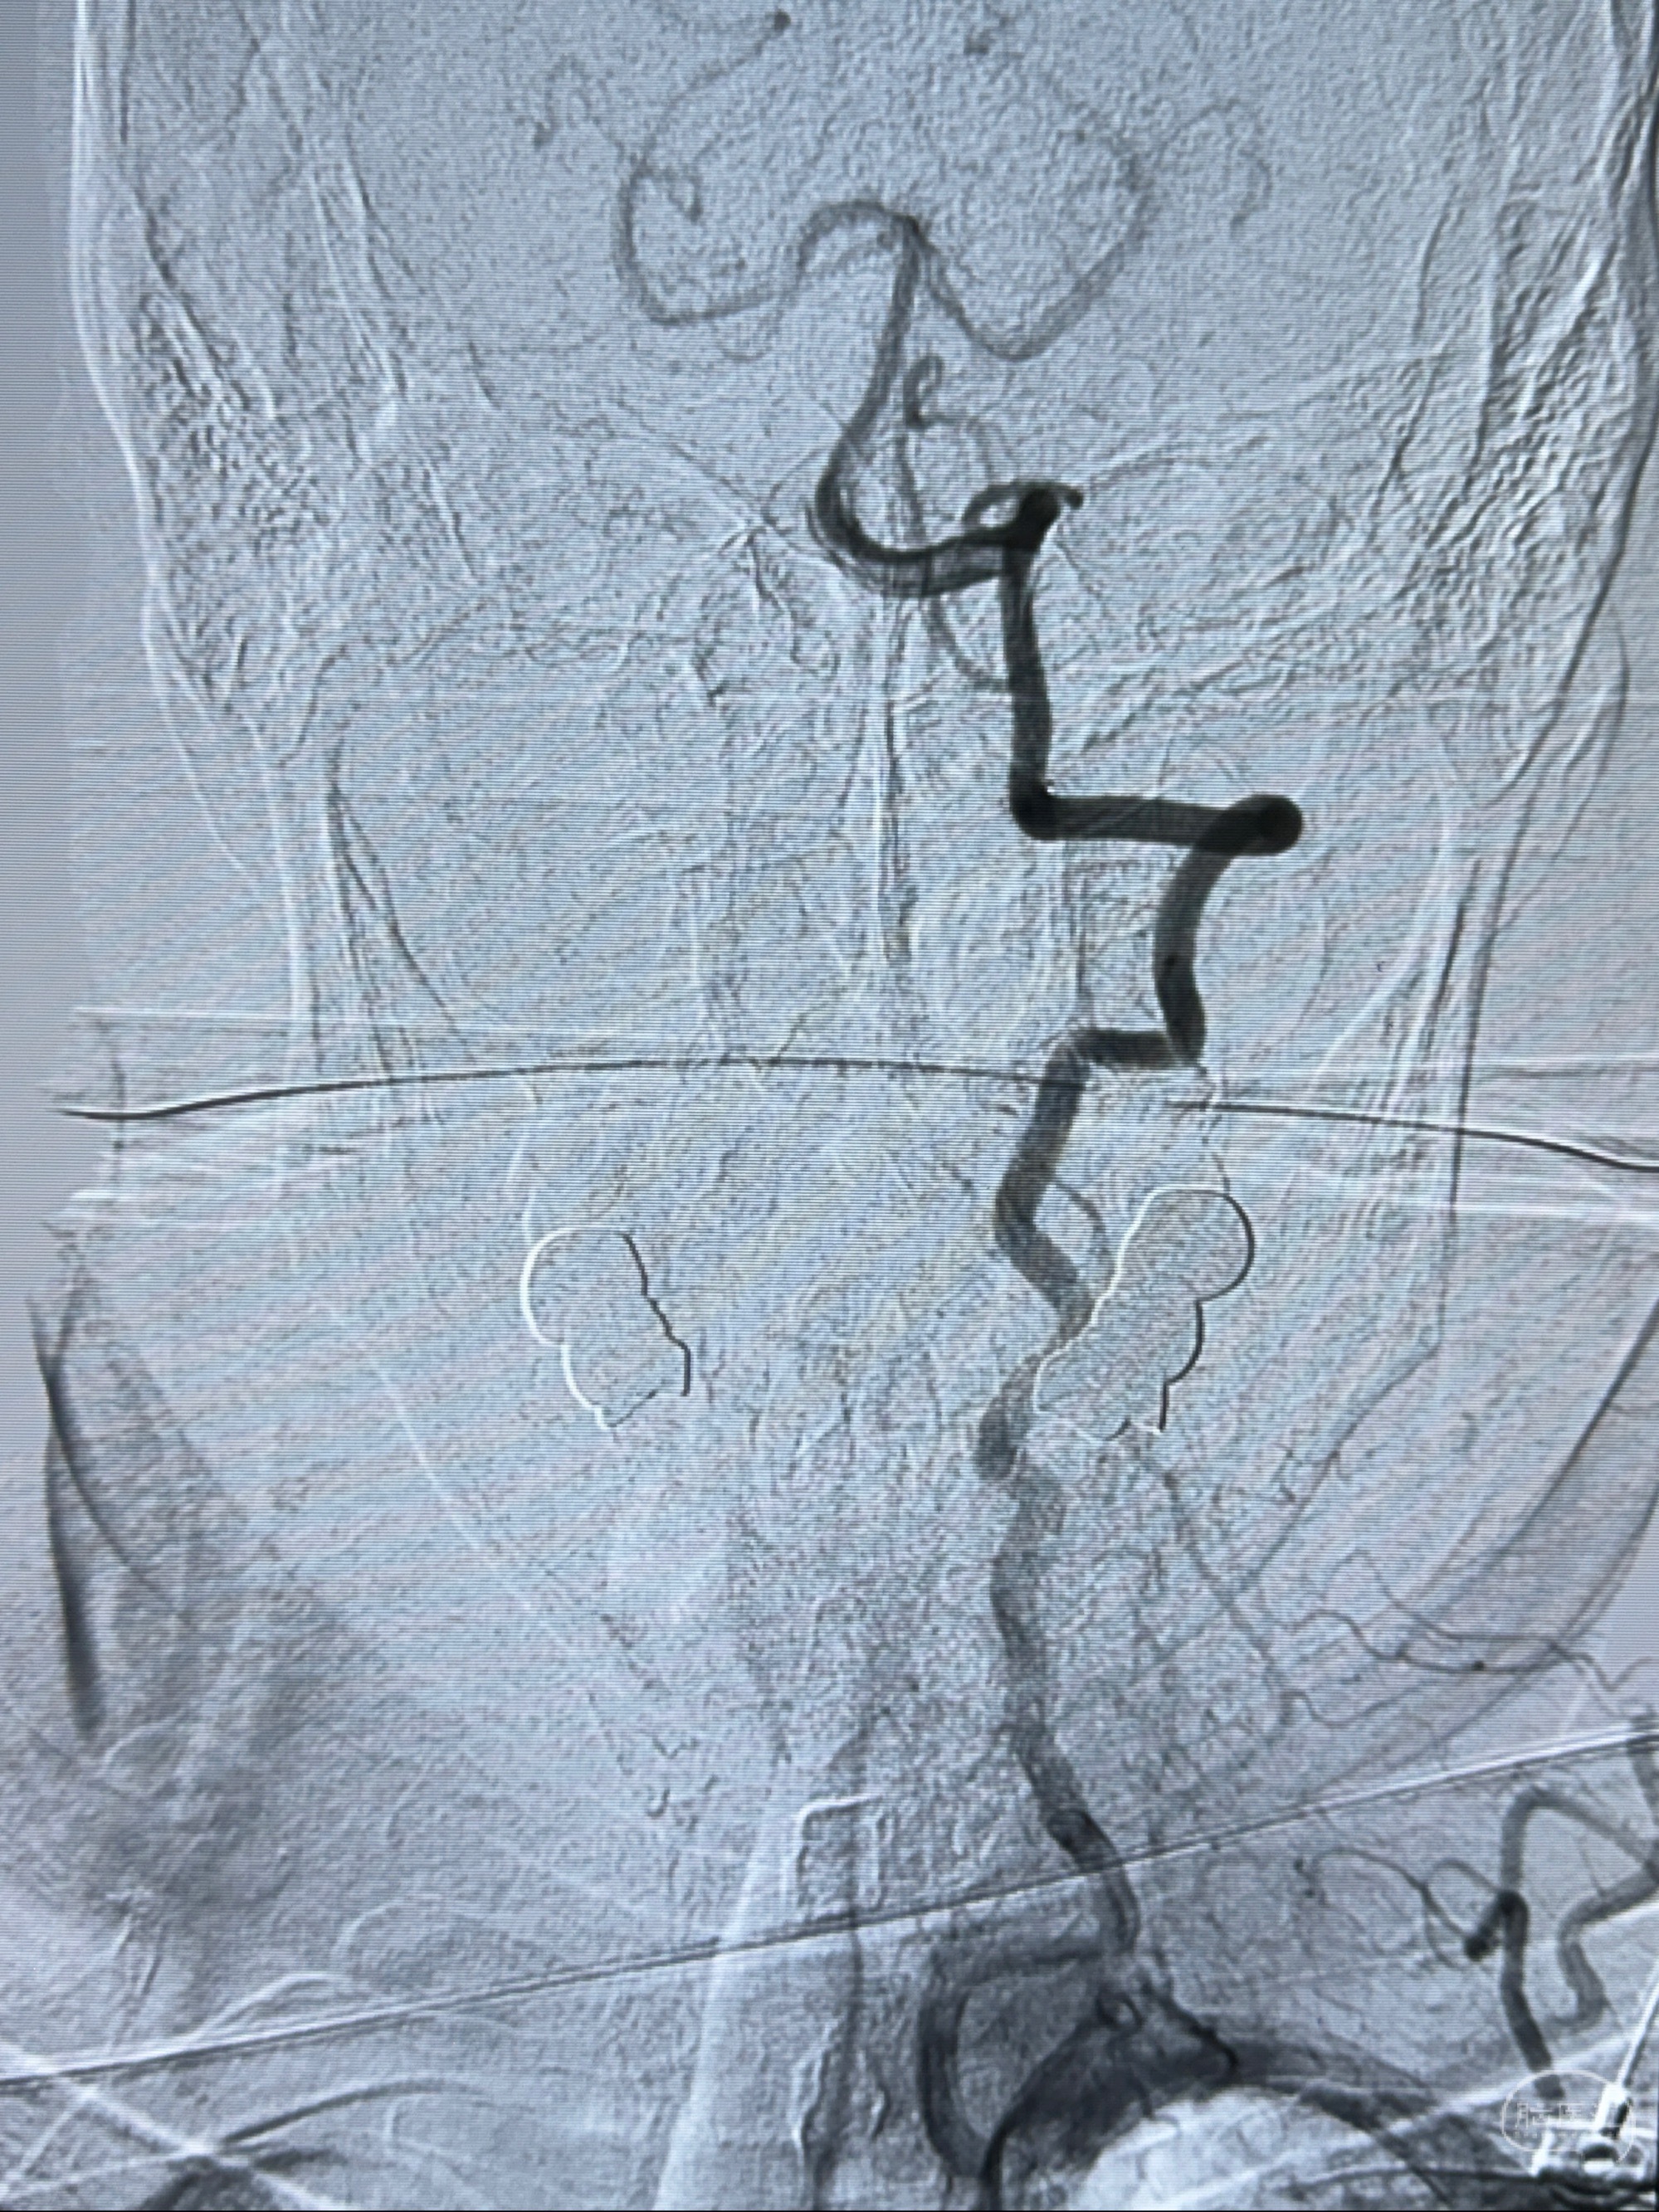

2023-11-24DSA:右侧大脑中动脉下干起始部动脉瘤,约2.3*2.5mm,形态规则

2023-12-04全麻下行支架辅助治疗

S-AB4-20mm